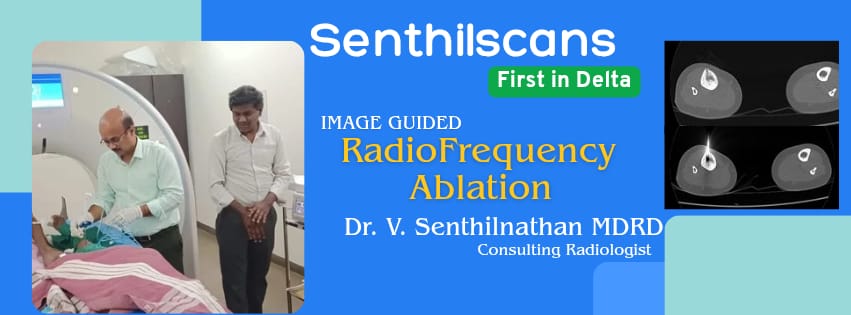

RadioFrequency Ablation - First in Delta